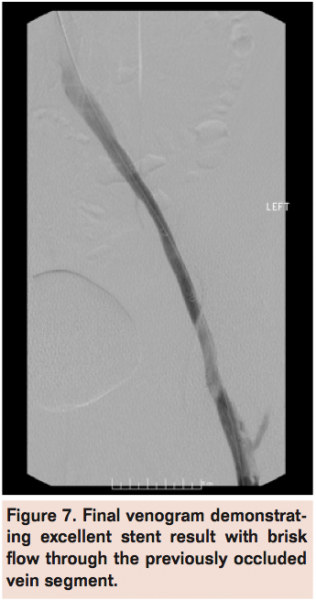

A Wildcat chronic total occlusion catheter (Avinger) was advanced in active and passive modes to traverse the occlusion (Figure 4) followed by a glidewire (Terumo) with confirmation of intraluminal position within the IVC via contrast injection (Figure 5). Serial balloon venoplasty was performed in ascending fashion using EverCross 6 mm x 100 mm, 7 mm x 120 mm, and 12 mm x 60 mm balloons (Covidien) and subsequent stenting with Protégé Everflex 12 mm x 80 mm and 8 mm x 150 mm self-expanding stents (Covidien) in overlapping fashion from the ostium of the left common iliac vein (Figure 6) to the common femoral vein. The entire stented segment was post-dilated with the EverCross 12 mm x 60 mm balloon and final venography demonstrated brisk flow through the left common femoral to common iliac vein stent (Figure 7).